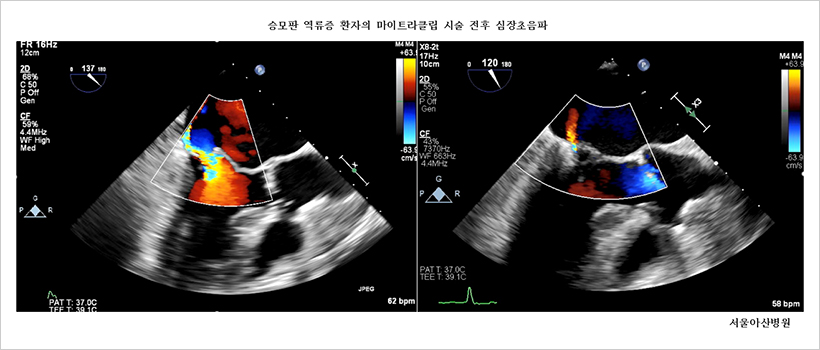

고위험 환자 가슴 여는 수술 없이 승모판 역류증 치료 가능서울아산병원 심장내과 박덕우·김대희·강도윤 교수팀, 마이트라클립 시술 국내 첫 성공

서울아산병원 심장내과 박덕우 · 김대희 · 강도윤 교수팀은 최근 82세 고령의 남성 환자 김 모 씨에게 국내에서 처음으로 승모판 역류증 치료용 기구인 마이트라클립(Mitraclip) 시술을 성공적으로 시행했다.

서울아산병원 심장병원 통합진료팀은 고위험군의 환자인 김 씨가 보다 안전하게 치료받을 수 있도록 개흉수술 없이 마이트라클립 2개를 승모판에 시술함으로써 승모판 역류증을 치료했으며, 회복기간도 짧아 김 씨는 시술 5일 후 퇴원했다.

김대희 서울아산병원 심장내과 교수는 “마이트라클립 시술은 3D 초음파로 클립의 정확한 위치와 승모판의 해부학적 구조를 실시간 확인하며 진행해야 해 의료진 간 긴밀한 협진이 필수적이다. 서울아산병원 심장병원의 통합진료 시스템과 다년간 축적된 국내 최다 중재시술 및 심초음파 경험 덕분에 좋은 결과를 얻을 수 있었다. 앞으로도 환자의 상태를 충분히 고려한 맞춤형 시술로 환자의 삶의 질을 높일 수 있도록 노력할 것”이라고 덧붙였다.